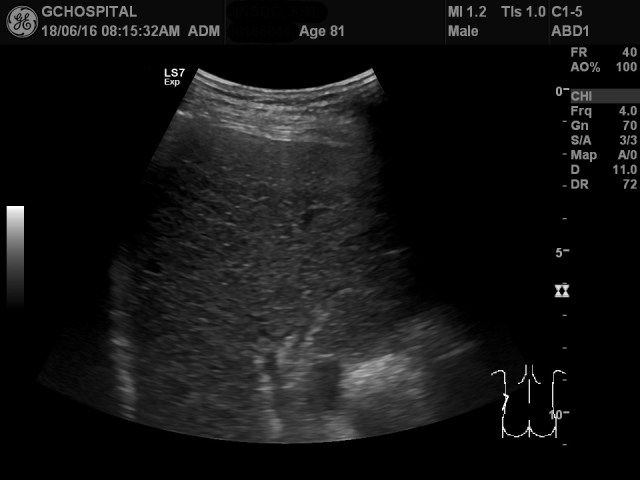

반대로 왼쪽 옆구리에서는 전형적인 우측 간문맥의 형태를 확인할 수 있었습니다.

결론적으로 뱃속의 장기의 좌우 위치가 바뀌는 situs inversus 위치이상 환자였습니다. 이러한 위치 이상 자체는 별다른 증상이 없고, 진단도 어렵지 않지만 막상 초음파검사를 통해서 처음 접할 때에는 혼란을 느낄 수 있기 때문에 이번 사례를 통해 미리 익숙해지는 것이 의미가 있을거라 기대합니다.